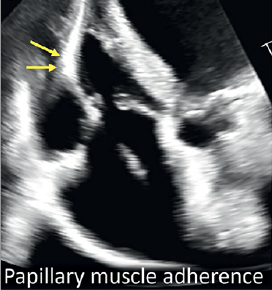

Laurence M. Epstein, MD; Rebecca T. Hahn, MD

"A heart team approach is mandatory, because these patients are very complicated and the leads may or may not be contributing to the tricuspid regurgitation," says Laurence Epstein, MD. Read more from Dr. Epstein and Rebecca Hahn, MD.

Basavanna Dinesh, MD, DM; Yamasandi Siddegowda Shrimanth, MD, DM; Aditha Cibi, MD; et al. Reprinted with permission from J INVASIVE CARDIOL 2024;36(8).